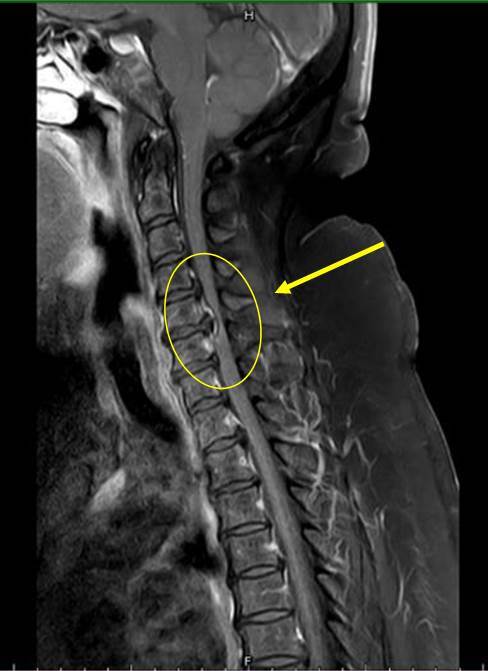

台中豐原一名47歲的吳姓女子,因長期腰酸背痛不適,近3個月開始下肢無力、麻痛,無法工作,甚至需使用四腳拐杖協助才能走動,在先生陪同至衛福部豐原醫院神經外科門診求治,經醫師做神經學評估及安排頸部核磁共振檢查,發現頸部退化椎間盤突出,導致壓迫神經使肢體麻痛無力,診療期間吳女跟醫師說,此次頸椎出問題,應該與自己長期胸部豐滿而導致,最終決定接受縮胸手術,成功解決困擾。

神經外科醫師張正一指出,身體為了平衡駝背,易導致頭部自動往前移,讓肩頸痠痛產生,外觀上易變成「永久低頭族」,如此易傷頸椎。因此,趙玟珊提醒民眾,造成下肢無力會有許多原因,必要時盡早求醫做檢查,甚至與醫師討論自身狀況,或許會有意外的發現,才能徹底改善原因,達到治療效果。